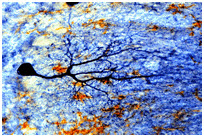

뇌의 신경세포

인체내의 다른 세포들과 달리 신경세포는 축색과 수상돌기를 갖고 인근 신경세포들과 시냅스를 형성하며 정보를 전송하면서 인체내의 정보 통신 시스템을 구축하고 있기 때문에 신경세포가 새로 만들어진다면, 이 세포가 어떻게 기존의 신경망에 참여하게 되고, 그 신경망에서 담당하던 일을 어떻게 계속하게 되는지 미지수이다. 이런 관점에서 성인 뇌에서 신경세포의 생성은 충격적인 사실이다.